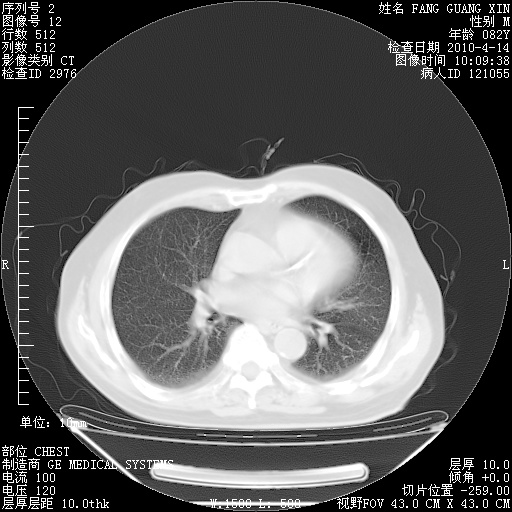

4月14日肺部CT

23.JPG

24.JPG

25.JPG

26.JPG